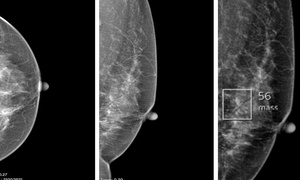

U xơ vú ở phụ nữ trẻ: Khi nào cần mổ, khi nào chỉ theo dõi?

Bệnh phụ nữ - 08/10/2025 05:51SKĐS - U xơ vú lành tính thường gặp ở phụ nữ trẻ, đa phần không nguy hiểm. Tuy nhiên, khi khối u lớn nhanh hoặc gây biến dạng, cần cân nhắc can thiệp sớm.

Phát hiện sớm ung thư vú nhờ công nghệ AI

Ung thư - 08/10/2025 12:02SKĐS - Ung thư vú đang ngày càng trẻ hóa. Nếu trước đây bệnh chủ yếu gặp ở phụ nữ trên 45 tuổi, thì nay nhiều ca được phát hiện ở độ tuổi 30–40, thậm chí dưới 30 tuổi. Tuy nhiên, ung thư vú có thể phát hiện sớm và điều trị hiệu quả.